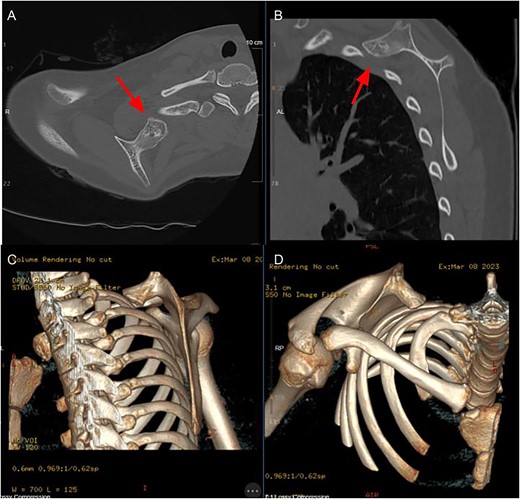

Here we describe a case of a 14-year-old healthy female who was referred to the orthopedic clinic reporting a 1-year history of right shoulder pain with mechanical locking symptoms. She noted discomfort and significant crepitus with shoulder abduction and overhead activities. She also noted a palpable deformity over the superior medial aspect of her shoulder. She was fully neurologically intact to her right upper extremity and her vascular exam was unremarkable. X-rays and a computed tomography scan were performed which demonstrated an osseous lesion at the superomedial ventral surface of the right scapula with cortical continuity with an associated cartilaginous cap, consistent with an osteochondroma (Fig. 1). A thorough discussion was held with the patient and her mother regarding treatment options and the decision was made to proceed with osteochondroma excision.

Axial (A) and sagittal (B) CT slices demonstrating lesion location, 3D reconstructions (C + D) further demonstrating morphology of lesion.